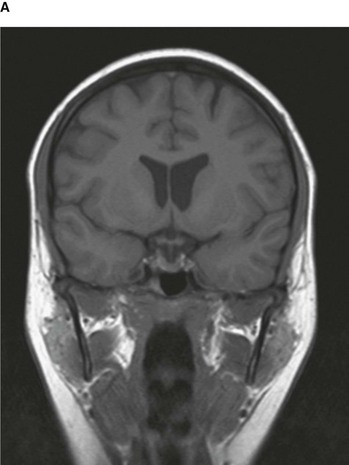

By altering the sequence of pulses to which the protons are subjected, different properties of the protons can be assessed. These properties are referred to as the “weighting” of the scan. By altering the pulse sequence and the scanning parameters, T1-weighted images (Fig. 1.10A) and T2-weighted images (Fig. 1.10B) can be obtained. These two types of imaging sequences provide differences in image contrast, which accentuate and optimize different tissue characteristics.

image image

Fig. 1.10 T1-weighted (A) and T2-weighted (B) magnetic resonance images of the brain in the coronal plane.

From the clinical point of view:

image Most T1-weighted images show dark fluid and bright fat—for example, within the brain the cerebrospinal fluid (CSF) is dark;

image T2-weighted images demonstrate a bright signal from fluid and an intermediate signal from fat—for example, in the brain the CSF appears white.